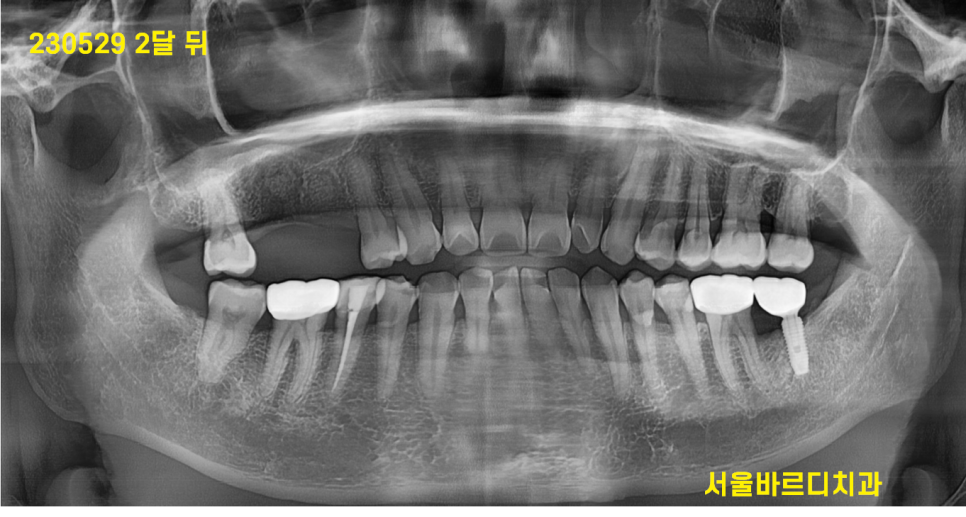

230529

약 2달 뒤 뼈가 잘 찼는지

확인하러 고덕동 치과를 방문해주셨는데요.

점점 잘 차오르고 아무는게 보입니다.

ct에서도 뼈이식한 흔적들이 잘 보입니다.

그렇지만 아직은 부족하여

2달을 더 기다립니다.